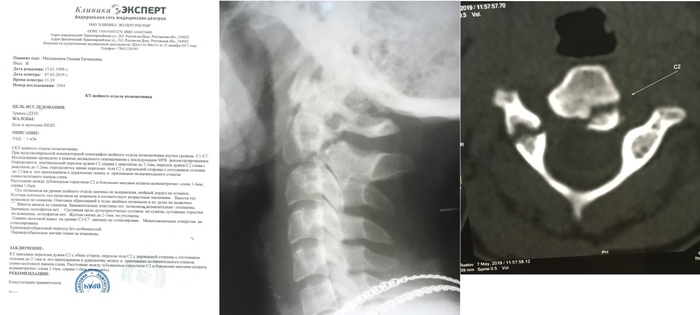

Здравствуйте всем. Пожалуйста, будьте осторожны при движении, за рулем могут быть пьяные сотрудники полиции!!! 01.05.2019 года в 22-50 на 61 километре автодороги "Ростов-Ставрополь" действующий сотрудник полиции, инспектор МРЭО ГИБДД Зерноград, старший лейтенант полиции Панасенко Александр Александрович (на прикрепленных фото и видео), управляя в нетрезвом состоянии автомобилем "УАЗ Патриот" (г/н Т438ТН 161 RUS), двигался по встречной полосе с выключенным освещением, после включил свет и совершил столкновение с автомобилем АЗЛК 214122 (г/н К881СЕ 161 RUS), в котором находился Малышкин Алексей Валерьевич, 1991 года рождения, со своей женой, Малышкиной Оксаной Евгеньевной, 1999 года рождения. Вследствие данного ДТП, к большому сожалению Панасенко, оба пассажира выжили и были с сознании, водитель самостоятельно позвонил 112 и вызвал скорую помощь. Водитель УАЗ, тем временем, запустил двигатель автомобиля, попытался скрыться. Выехать не удалось, так как у автомобиля была деформирована и порвана рама, поврежден и вырван передний мост. После этого водитель УАЗ выбежал из автомобиля и попытался скрыться в лесополосе, но был замечен очевидцами ДТП. Водитель автомобиля АЗЛК Малышкин Алексей Валерьевич получил телесные повреждения средней тяжести (закрытая черепно-мозговая травма, многочисленные ушибы и ссадины), повлекшие кратковременные расстройства здоровья, пассажирка Малышкина Оксана Евгеньевна, получила тяжкие телесные повреждения (перелом второго позвонка шейного отдела позвоночника в трех местах со смещением, закрытая черепно-мозговая травма, множественные рассечения мягких тканей кожи лица, многочисленные ушибы и ссадины). Водитель УАЗ Панасенко Александр Александрович видимых повреждений не получил, самостоятельно передвигался по территории места ДТП, в помощи медицинский работников не нуждался. После его звонка на место прибыли другие сотрудники ДПС МРЭО Зерноград во главе с начальником МРЭО.